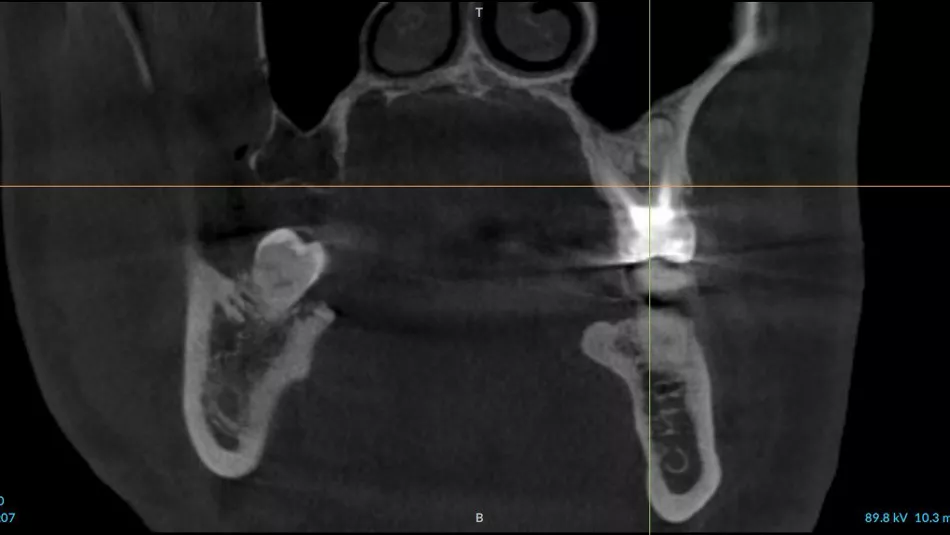

3a. 3b. 3c. 3D volumetric diagnosis and planning of implant therapy.

3a

3b

3c

4. Radiograph exhibiting a suitable septum for immediate implant placement.

4